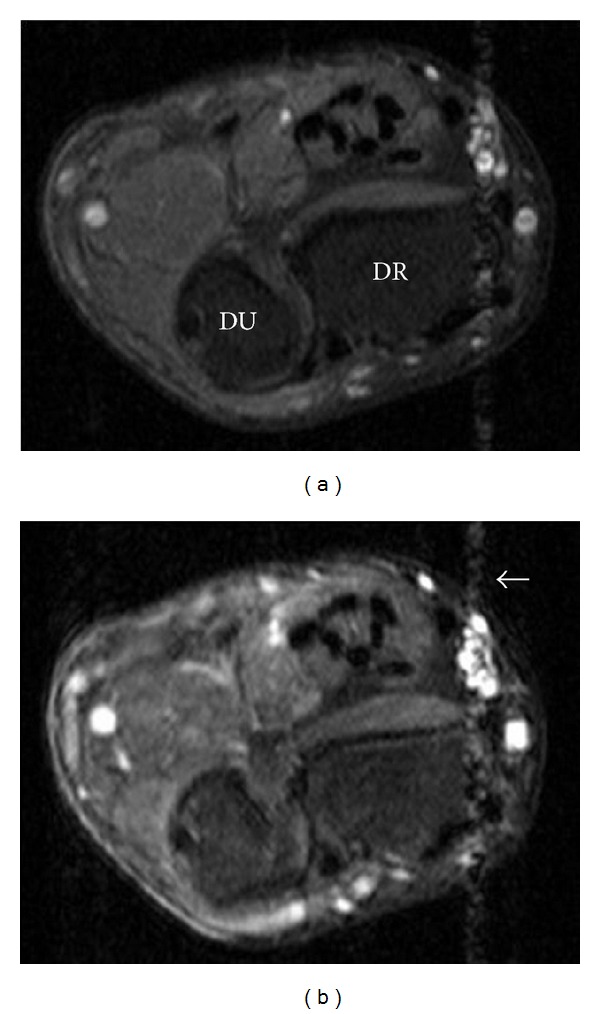

Figure 5.

Axial T1-weighted wrist MRI with fat suppression—(5a) precontrast, (5b) postcontrast: the majority of the lesion (seen more clearly on T2-weighted image; Figure 2) showed no significant enhancement. Pulsation artifact from radial artery (white arrow). DR: distal radius; DU: distal ulna.